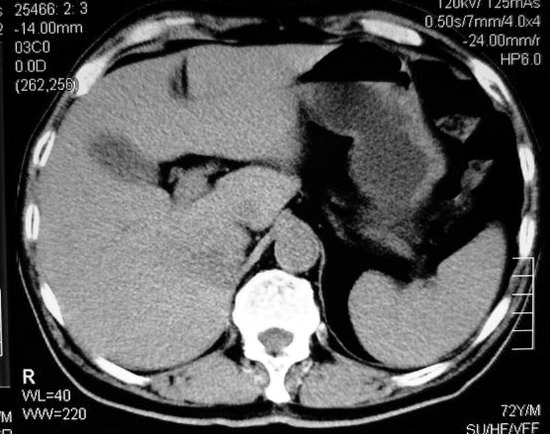

以下是引用杀毒软件在2008-11-17 19:15:00的发言:[br]考虑------右肾癌合并肾静脉---同侧肾上腺受侵可能性大

以下是引用zjzjr在2008-11-17 20:45:00的发言:[br]考虑------右肾癌合并肾静脉---同侧肾上腺受侵可能性大及腹膜后淋巴结转移.